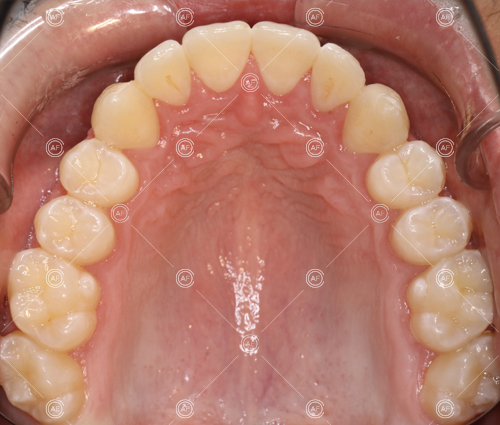

MH debonded in December 2020, with overall treatment time of around 14 months.

She was provided with upper and lower vacuum form retainers, and asked to wear these every night for the first year, and alternate nights for the second year onwards, indefinitely for as long as she wanted her teeth to remain straight. High quality finish was maintained at one year post-debond.